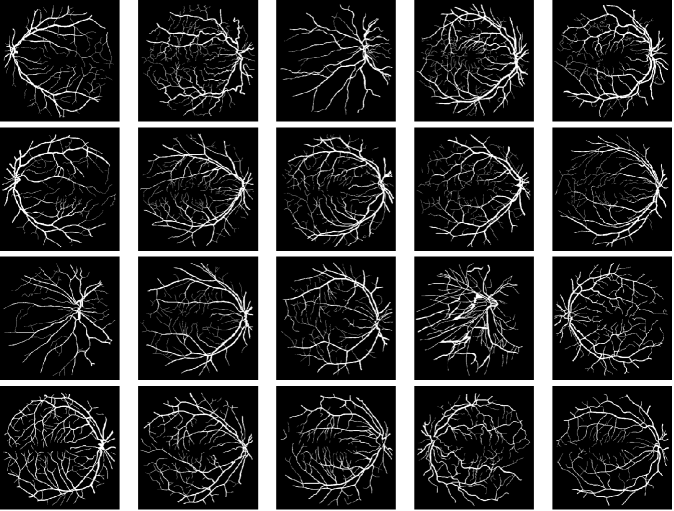

In this paper, we aim to segment an image degraded by blur and Poisson noise. We adopt a smoothing-and-thresholding (SaT) segmentation framework that finds a piecewise-smooth solution, followed by k𝑘k-means clustering to segment the image. Specifically for the image smoothing step, we replace the least-squares fidelity for Gaussian noise in the Mumford-Shah model with a maximum posterior (MAP) term to deal with Poisson noise and we incorporate the weighted difference of anisotropic and isotropic total variation (AITV) as a regularization to promote the sparsity of image gradients. For such a nonconvex model, we develop a specific splitting scheme and utilize a proximal operator to apply the alternating direction method of multipliers (ADMM). Convergence analysis is provided to validate the efficacy of the ADMM scheme. Numerical experiments on various segmentation scenarios (grayscale/color and multiphase) showcase that our proposed method outperforms a number of segmentation methods, including the original SaT.

Image segmentation partitions an image into multiple, coherent regions, where pixels of one region share similar characteristics such as colors, textures, and edges. It remains an important yet challenging problem in computer vision that has various applications, including magnetic resonance imaging [26, 40, 62] and microscopy [7, 81]. One of the most fundamental models for image segmentation is the Mumford-Shah model [50] because of its robustness to noise. Given an input image f:Ω:𝑓Ωf:\Omega\rightarrow\mathbb{R} defined on an open, bounded, and connected domain Ω2Ωsuperscript2\Omega\subset\mathbb{R}^{2}, the Mumford-Shah model is formulated as

• We conduct numerical experiments on various grayscale/color images to demonstrate the effectiveness of the proposed approach.